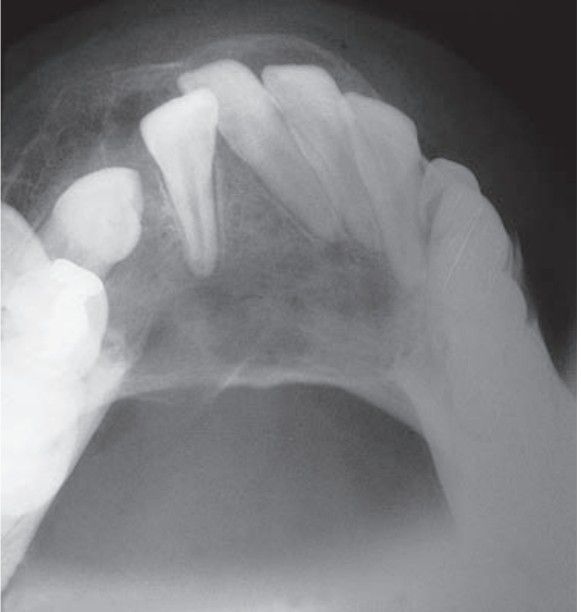

Central giant cell granuloma

May exhibit aggressive behavior; low recurrence rate; asymptomatic.